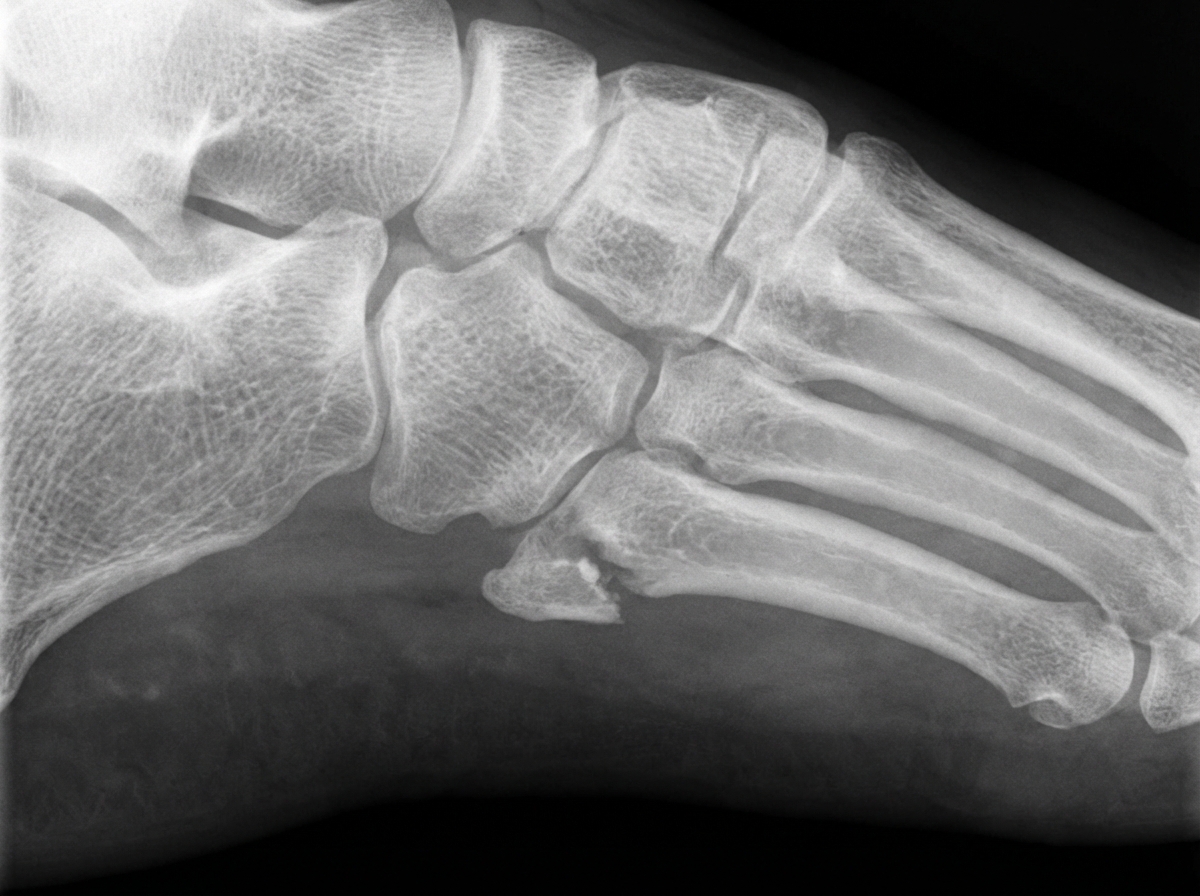

A 45-year-old male presents with foot pain after an injury. What is the mechanism of injury associated with the pathology seen in this X-ray?

Explanation: ***Inversion of the foot producing tension on the peroneus brevis tendon*** - Inversion of the foot creates strong **traction** on the **peroneus brevis tendon**, which inserts at the base of the 5th metatarsal, causing an **avulsion fracture** of the styloid process. - This mechanism is the classic cause of a **5th metatarsal base avulsion fracture**, commonly seen in ankle sprains with significant inversion force. *Forcible inversion of the foot in plantar flexion, such as in a dancer's injury* - This mechanism typically causes a **Jones fracture** at the **metaphyseal-diaphyseal junction** of the 5th metatarsal, not at the styloid process. - **Dancer's fractures** occur more distally in the metatarsal shaft due to **repetitive stress** rather than acute avulsion. *Fall while climbing stairs or falling from a height* - These mechanisms typically result in **calcaneal fractures**, **ankle fractures**, or **metatarsal shaft fractures** from axial loading. - The injury pattern would show **compression** or **bending forces** rather than the characteristic **avulsion pattern** at the 5th metatarsal base. *A direct blow* - Direct trauma typically causes **transverse fractures** of the metatarsal shaft or **crush injuries** to the forefoot. - This mechanism would not specifically target the **styloid process** of the 5th metatarsal base where the peroneus brevis inserts.